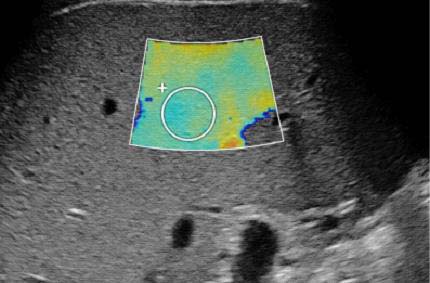

Представляем ряд клинических примеров, демонстрирующих определение степени фиброза печени с помощью SWE у беременных с HBV- и HCV-инфекциями (рис. 1–5).

Рис. 3. Беременная Р.Р., G2P2A0, позитивна по вирусу гепатита В, результат сдвигововолновой эластографии печени: METAVIRSTAGE — F2

Обследование проводили в положении пациентки на спине с уклоном влево. Датчик располагали в восьмом-девятом межрёберном промежутке по правой передней и задней подмышечной линии. Плотность ткани определяли в правой доле на бессосудистом участке на глубине 2 см от капсулы, результаты выражали в килопаскалях. Полученные показатели плотности тканей оценивали по шкале METAVIR: <7,1 кПa — F0–F1; 7,1–7,9 кПa — F2; 8,0–10,4 кПa — F3; >10,4 кПa — F4), где F0 — отсутствие фиброза; F1 — расширение портального тракта без септ; F2 — портальный фиброз с небольшим количеством сформированных септ; F3 — портальный фиброз с формированием множественных септ; F4 — цирроз печени.